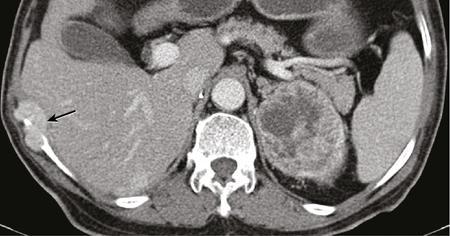

IMAGING OF RENAL MALIGNANCIES IN ADULTS Aparna Katdare, Palak Bhavesh Popat, Nilesh P. Sable, Ganesh Bakshi, Suyash Kulkarni Detection of renal masses has increased remarkably in recent times owing to wide-spread use of cross-sectional imaging. Imaging plays an important role in characterizing renal masses and is indispensable in treatment planning in renal malignancies. The most commonly encountered malignant renal masses in practice include renal cell carcinoma (RCC), urothelial carcinoma, lymphoma and metastases. Urothelial carcinoma and lymphoma have been covered in detail in separate chapters. RCC constitutes nearly 90% of all renal malignancies with a higher incidence in North America and Europe than India, Africa and China. With an increase in the number of cross-sectional studies performed, especially in Western population, the incidental diagnosis of RCC has increased in recent times, with such incidentally diagnosed lesions presenting at earlier stages with better prognosis and reduced rates of recurrence. The median age of presentation of RCC is 64 years according to the Surveillance, Epidemiology and End Results (SEER) program database and almost a decade earlier in Indian population, with a definite increasing risk of RCC with increasing age. Males are affected about 2–3.5 times more than females. In the Indian population, patients have been seen to present at a later stage as compared to the Western population. Amongst the various postulated risk factors, there is convincing evidence that smoking, hypertension, obesity and acquired renal cystic disease increase the risk of RCC. Alcohol intake and physical activity have been found to be associated with reduced risk of RCC. Trichloroethylene and cadmium exposure have been postulated as likely causes as well. Two to four per cent of RCCs are hereditary, with association of various genetic disorders such as Von Hippel Lindau (VHL) syndrome, hereditary papillary renal carcinoma, hereditary leiomyomatosis RCC, Birt-Hogg-Dube syndrome, chromosome 3 translocation and tuberous sclerosis (TCS1, TCS2). The WHO classification of 2016 (Table 11.25.1.1) stratifies tumours of the kidney into different subtypes based on cytoplasmic and architectural features, tumour location, background renal disease and molecular alterations. Clear cell renal cell carcinoma Multilocular cystic renal neoplasm of low malignant potential Papillary renal cell carcinoma Hereditary leiomyomatosis and renal cell carcinoma-associated renal cell carcinoma Chromophobe renal cell carcinoma Collecting duct carcinoma Renal medullary carcinoma MiT family translocation renal cell carcinomas Succinate dehydrogenase-deficient renal carcinoma Mucinous tubular and spindle cell carcinoma Tubulocystic renal cell carcinoma Acquired cystic disease-associated renal cell carcinoma Clear cell papillary renal cell carcinoma Renal cell carcinoma, unclassified Papillary adenoma Oncocytoma 8310/3 8316/1a 8260/3 8311/3* 8317/3 8319/3 8510/3a 8311/3a 8311/3 8480/3a 8316/3a 8316/3 8323/1 8312/3 8260/0 8290/0 Metanephric adenoma Metanephric adenofibroma Metanephric stromal tumour 8325/0 9013/0 8935/1 Nephrogenic rests Nephroblastoma Cystic partially differentiated nephroblastoma Paediatric cystic nephroma 8960/3 8959/1 8959/0 Clear cell sarcoma Rhabdoid tumour Congenital mesoblastic nephroma Ossifying renal tumour of infancy 8964/3 8963/3 8960/1 8967/0 Leiomyosarcoma Angiosarcoma Rhabdomyosarcoma Osteosarcoma Synovial sarcoma Ewing sarcoma Angiomyolipoma Epithelioid angiomyolipoma Leiomyoma Haemangioma Lymphangioma Haemangioblastoma Juxtaglomerular cell tumour Renomedullary interstitial cell tumour Schwannoma Solitary fibrous tumour 8890/3 9120/3 8900/3 9180/3 9040/3 9364/3 8860/0 8860/1a 8890/0 9120/0 9170/0 9161/1 8361/0 8966/0 9560/0 8815/1 Cystic nephroma Mixed epithelial and stromal tumour 8959/0 8959/0 Well-differentiated neuroendocrine tumour Large cell neuroendocrine carcinoma Small cell neuroendocrine carcinoma Phaeochromocytoma 8240/3 8013/3 8041/3 8700/0 Renal haematopoietic neoplasms Germ cell tumours The morphology codes are from the International Classification of Diseases for Oncology (ICD-O) {917A}, Behaviour is coded/0 for benign tumours; /1 for unspecified, borderline or uncertain behaviour; /2 for carcinoma in situ and grade III intraepithelial neoplasia; and /3 for malignant tumours. The classification is modified from the previous WHO classification (756A), taking into account changes in our understanding of these lesions. aNew code approved by the IARC/WHO Committee for ICD-O. Of these, the most common entity is the clear cell subtype, while papillary and chromophobe subtypes are less common. The different subtypes show varied biological behaviour, treatment response and prognosis. The 2017 guidelines by American Urological Association (AUA) as well as 2019 guidelines by European Society of Medical Oncology (ESMO) recommend multiphase cross-sectional imaging by either CT or MRI for renal mass characterization and staging. AUA 2017 guidelines recommend renal mass characterization on the basis of tumour complexity, contrast enhancement and presence or absence of fat. MRI has an upper hand over CT in characterizing subtle mass enhancement, cystic lesions and lesions less than 2 cm. ESMO recommends contrast-enhanced CT study of the chest, abdomen and pelvis for renal mass staging. Bone scan and brain CT or MRI can be considered if indicated by clinical or laboratory investigations. For characterization of renal masses, a multiphase CT or MRI study is recommended. CT study constitutes an unenhanced study followed by contrast injection and acquisition of corticomedullary phase at 40 seconds, nephrographic phase at around 100 seconds and delayed phase at around 5 minutes. MRI protocol includes T2-weighted single-shot fast spin-echo 2D sequences, axial T1-weighted 2D sequence with in-phase and opposed-phase gradient echo imaging, precontrast and postcontrast imaging with a 3D T1-weighted spoiled gradient recalled sequences in corticomedullary phase at 30 seconds, nephrographic phase at 100 seconds, 180–210 seconds and delayed phase imaging at 5 minutes and diffusion-weighted imaging with multiple b-values 0–50, 400–500 and 800–1000 s/mm2. The ACR White Paper on CT imaging of incidental renal mass recommends using the following descriptors for characterizing renal masses: Given the prognostic implications, it is worthwhile for radiologists to know the imaging features that may help discriminate between the common histological subtypes of RCC on various imaging modalities. This is the most common histological type of RCC, accounting for about 70% of cases. These are exophytic tumours with a heterogeneous appearance due to the presence of necrosis, intratumoural haemorrhage, cystic components with septations and calcific foci and hence have a more heterogeneous appearance on cross-sectional imaging than the other subtypes (Fig. 11.25.1.1). Necrosis is seen more often in larger masses and higher tumour grades (Fig. 11.25.1.2). On CT, depending on the tumour composition, these are seen as heterogeneous lesions, show marked contrast enhancement in the corticomedullary phase with washout on nephrogenic phase (Fig. 11.25.1.2). On MRI, these characteristically show high signal intensity on T2W sequences (Fig. 11.25.1.3). The presence of intracytoplasmic fat in the clear cells of the tumour is reflected in the loss of signal in opposed phase images on chemical shift imaging, which is seen in nearly 60% of these tumours. A pseudocapsule may be seen, which is best appreciated on T2-weighted imaging on MRI; the presence of a pseudocapsule has a high negative predictive value for perinephric extension (Figs. 11.25.1.3 and 11.25.1.4). Conversely, larger tumours with higher grades often have interrupted pseudocapsule and hence tend to be irregular, spread into the perinephric fat with renal vein and inferior vena cava (IVC) invasion (Figs. 11.25.1.5 and 11.25.1.6). On diffusion-weighted imaging, clear cell RCCs have been seen to have higher ADC values than nonclear cell RCCs, and lower-grade tumours have been seen to have higher ADC values than higher-grade tumours. The clear cell variant has worse prognosis than the papillary and chromophobe subtypes, presenting at a more advanced stage and being more likely to recur or metastasize (Fig. 11.25.1.7), with lower 5-year survival rates at 44%–69% as compared to 78%–92% for the other two. Papillary RCC comprises about 10%–15% of RCCs. These are slow-growing tumours and hence are well-marginated in contrast to clear cell RCC. As they are hypovascular, their enhancement on CT is significantly less than clear cell RCC (Fig. 11.25.1.8). These show characteristically low signal on T2W images on MRI (Fig. 11.25.1.9). Intracytoplasmic or macroscopic fat is less often seen on MRI imaging as compared to the clear cell variants. Larger tumours tend to be more heterogeneous (Fig. 11.25.1.10). These tumours may sometimes show cystic appearances, mural projections or blood degradation products. Calcifications are more common in papillary variants than clear cell RCC. Multifocality and bilaterality are also more common in these tumours than clear cell variants. These account for about 5% of RCCs. These are less aggressive, more homogeneous and hypovascular lesions than clear cell variants, with intensity of contrast enhancement on cross-sectional imaging being midway between clear cell and papillary variants. They show low to intermediate T2 signals on MRI. A characteristic feature is the presence of a central scar and spoke-wheel enhancement, the latter being a histopathological and imaging similarity between these tumours and oncocytoma (Fig. 11.25.1.11). Other subtypes of RCC are much less common but some may show distinct imaging findings. Multilocular cystic RCCs have excellent prognosis and lack mural nodules within the cystic components, unlike clear cell RCCs with cystic degeneration which show mural nodules. Collecting duct carcinomas, on the other hand, are aggressive tumours with poor prognosis and have medullary origin, and therefore appear similar to transitional cell carcinomas on imaging. Medullary RCCs are associated with sickle cell disease and sickle cell trait and are seen as infiltrating intracalyceal obstructive lesions with associated nodal disease. The imaging work-up of a suspected RCC is aimed at: Localized renal cancer is defined as a disease confined to the renal capsule and refers mainly to stage I and II disease. Nearly 70% of RCCs, especially the lower-stage lesions, are incidentally diagnosed on cross-sectional imaging. Also, amongst incidentally diagnosed renal lesions less than 4 cm in size, about 20% turn out to be benign on histopathology. Asymptomatic incidentally diagnosed small renal masses have an indolent course and better prognosis. Nephron-sparing surgery (NSS) has gathered momentum in recent years due to promising results and prognoses in small lesions. The 2017 AUA guidelines for localized renal masses describe restricted and well-defined indications for radical nephrectomy, bigger role of nephron-sparing procedures such as partial nephrectomy, tumour enucleation and thermal ablation, as well as increasing role for biopsy as well as active surveillance of such lesions. Hence, imaging findings in these lesions become critical in charting management of these patients. The imaging features of common histopathological subtypes of RCCs have already been discussed above. Signal intensity on T2W images and corticomedullary phase enhancement have been seen to be independent predictors of clear cell and papillary RCCs. Further, T2 signal homogeneity can be a predictor for slower growth rate. Hence, in general, multiparametric MRI studies have been shown to be effective in small renal mass characterization and can subsequently guide decisions regarding biopsy, surgery or surveillance. CT is a good alternative in patients with contraindication to MRI. For cystic renal lesions, the Bosniak classification, which stratifies the risk of neoplasia in cystic renal lesions based on the complexity of their appearance (wall thickness, septations, solid component), can be used effectively to decide further course of management. The Bosniak classification originally applies to CT findings but can logically be extrapolated to MRI, USG and Contrast Enhanced Ultrasound (CEUS) as well. Bosniak I and II cysts are benign while Bosniak IIF, III and IV cysts show progressively increasing risk of neoplasia. Given the more indolent course of cystic RCCs as compared to solid lesions and possible complications of interventions, lately there has been a case for even the type III and IV cysts, which previously would be operated, to be followed up, especially if patient has existing comorbidities or if the solid component is minimal. Initial follow-up would be at 6 months, followed by annual imaging. AUA 2017 guidelines recommend considering renal mass biopsy if haematologic, metastatic, inflammatory or infectious aetiology is suspected. Once the need for surgery is established in a localized disease, NSS may be considered for stage Ia and Ib disease. To predict perioperative outcomes in NSS, various scoring systems have been proposed for preoperative renal mass evaluation, such as R.E.N.A.L. nephrometry score, PADUA score (Preoperative aspects and dimensions used for anatomical classification), C-index method and mathematical tumour contact surface area (CSA). The popular R.E.N.A.L. nephrometry score takes into account various tumour descriptors that help decide the technical feasibility of NSS and predict surgical outcomes. These include tumour radius, exo/endophytic location, nearness to collecting system or renal sinus, anterior/posterior location and location with reference to polar lines. These descriptors need to be commented upon diligently while reporting renal masses (Table 11.25.1.4). Higher scores are seen to correlate with ischaemia time, postoperative urologic complications, higher grade and mortality. These include organ-confined tumours more than 7 cm in size, or tumours of any size which show regional nodal involvement and/or invasion of perinephric tissues but confined to Gerota’s fascia. These include renal vein and IVC invasion (luminal and mural). Generally, radical nephrectomy is recommended by the National Comprehensive Cancer Network (NCCN) in stage II and III RCCs. Both CT and MRI are effective in diagnosing locally advanced disease in RCC. The loss or interruption of pseudocapsule is seen in more infiltrative and aggressive disease and is best seen on MRI. Local infiltration may be in the form of contiguous spread to perinephric tissues or discrete deposits in perinephric fat (Fig. 11.25.1.15). IVC or renal vein invasion could be in the form of intraluminal thrombosis or invasion of the vessel wall and have implications on surgical approach and outcomes. Tumour thrombus can be distinguished from bland thrombus by confirming vascularity within the thrombus on imaging. Doppler evaluation, CEUS, CT and MRI can all be helpful for the same. MRI is better than other modalities for venous evaluation, especially for mural invasion and IVC invasion (Figs. 11.25.1.16 and 11.25.1.17). Right-sided tumours, anteroposterior IVC diameter of 2.4 cm or more at the level of renal hilum and complete IVC occlusion at this level are associated with higher risk of IVC resection. About 16% of patients with RCC have metastases at diagnosis and about 20%–30% of patients operated for local disease develop recurrence or metastases at a later date. The recurrent disease occurs most commonly within 3 years of diagnosis and uncommonly even later in young patients or large tumours. The most common sites of metastases from RCC are lungs, liver, bones, nodes, adrenals and brain. CT scan is the preferred modality for primary staging and surveillance for metastases because of its widespread availability and versatility for diagnosing bone and soft tissue lesions. MRI is preferred for looking for recurrence in postablative lesions, wherein these are seen as new enhancing lesions or show increase in the size of preexisting enhancing components. 18FFluorodeoxyglucose – Positron Emission Tomography (PET)/CT and PET/MRI may be helpful to look for metastatic disease as well. 18FSodium fluoride – PET/CT has been found to be better than CT and bone scan in detecting osseous metastases. RCC is a relatively radiation-resistant tumour, and treatment options tilt in favour of surgical procedures for localized and locally advanced diseases. For metastatic disease, post-risk assignment, the treatment has to be planned. Treatment can be offered as per size and the clinical stage.